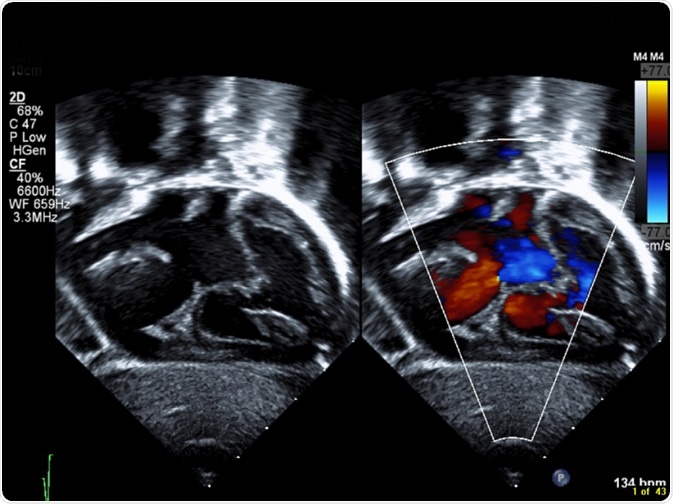

Congenital heart disease (CHD) is a broad term, which is used to describe several cardiac defects that may be found at birth, and affects proper heart function to varying degrees.

CHD is the most prevalent inborn disorder found in new-born babies, and it is the main cause of death from congenital birth defects in the perinatal period and during infancy. It is estimated that CHD may occur in up to as many as 13 in every 1000 live births, and mortality, as well as morbidity, are largely dependent on early diagnosis and timely transfer to specialized institutions with the necessary capacity to treat these conditions.

CHD may present with an array of signs and symptoms, some of which may be apparent immediately after birth, and others may not be until later in childhood or even early adulthood. Among these signs and symptoms is a cyanotic appearance, which is a bluish tinge to the skin, due to inadequate oxygen flow throughout the tissues.

Although there are many different CHDs, they may be grouped into CHDs that cause septal defects, narrowing of the aorta, narrowing of the pulmonary valve, transposition of the main vessels of the heart, and underdevelopment of the heart.

Septal defects are colloquially known as “holes” in the heart. These arise when there are abnormal connections between any of the heart’s chambers, which normally only communicate via a system of valves that open and close with contraction of the heart.